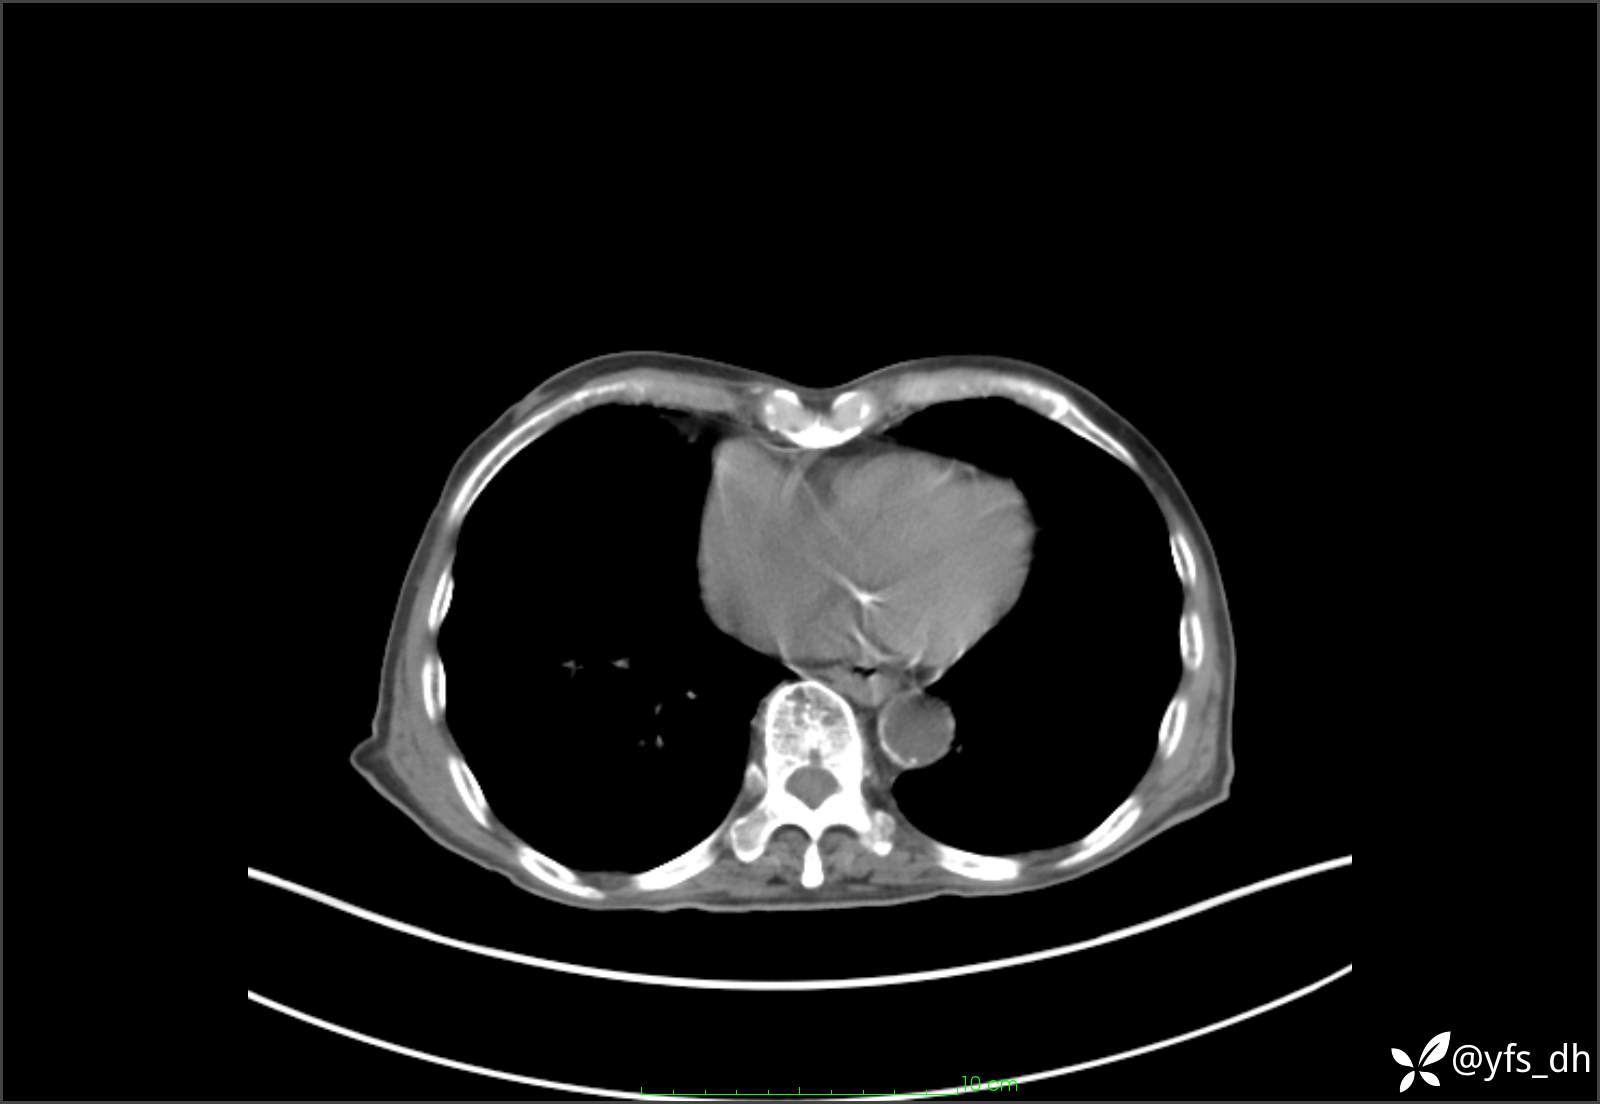

1.简要病史:患者4天前突发上腹部疼痛不适,但可以忍受。3小时前饭后突然加重,不能忍受后就诊。

2.简要手术记录:术中见腹盆腔大量肠液及粪便,乙状结肠中下段见一约3cm的破口。